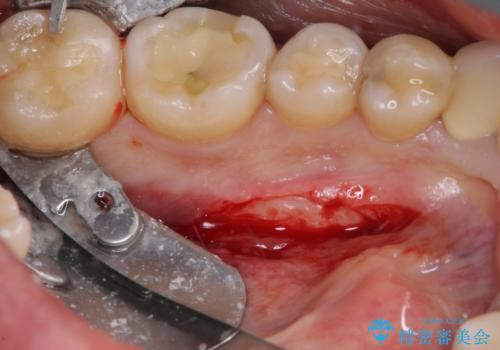

- 張り出している骨隆起による話しにくさを気にして来院された患者様です。

目視でも大きいと分かる骨隆起が認められたため、歯肉を切開した上で切除することとしました。

舌の下方に対する外科処置であるため、術後に飲み込みが辛くなったり、顎の下に痛みを感じたりすることがあります。